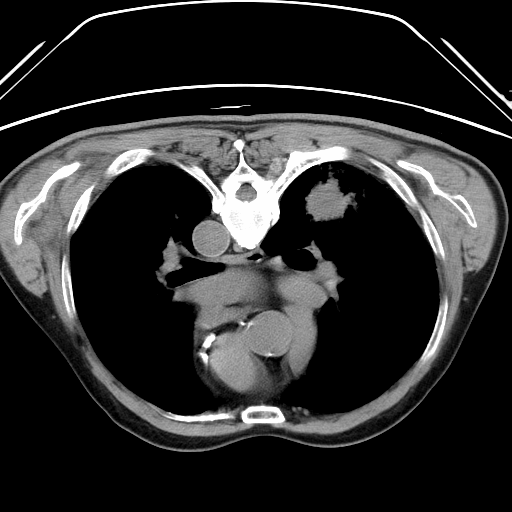

CT扫描提示右侧周围型肺癌

该患者因长期吸烟,反复咳嗽,通过病理确诊为右侧周围型肺癌,考虑到患者年龄大,长期患高血压糖尿病,同时合并肾功能不全,承受不住手术风险及术后化疗,因此转入我院微创介入科施行CT引导下肺癌射频消融治疗术。

通过局部消毒,局部麻醉后在CT引导下将直径2毫米射频针准确刺入肿瘤中心,10分钟后结束治疗,术中患者无明显不适,术后患者自行走回病房,3天后出院。